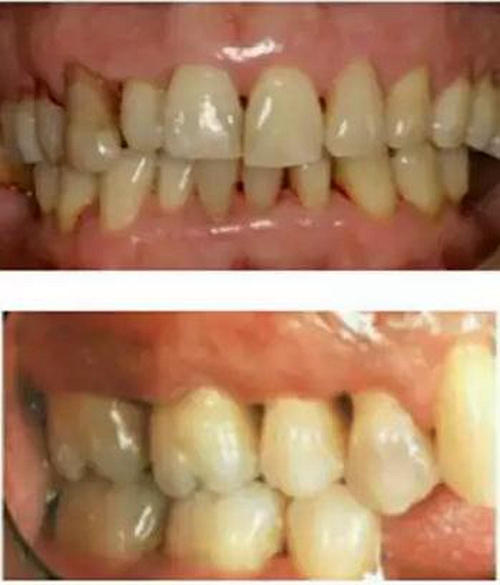

在猶疑之中,在未作任何牙周治療的情況下,牙齦出血可能突然減少或停止,很多患者慶幸自己的牙齦出血好了,其實是牙周病更加加重了,因為牙齦過度腫脹后,營養(yǎng)終于跟不上,導致了毛細血管的萎縮,因此會出現(xiàn)牙齦出血減少或停止的現(xiàn)象。但是同時牙槽骨也在喪失,于是,牙縫變稀變大(如上圖所示),更易殘留食物,口臭加重,牙根部分暴露,可能有冷熱刺激敏感。